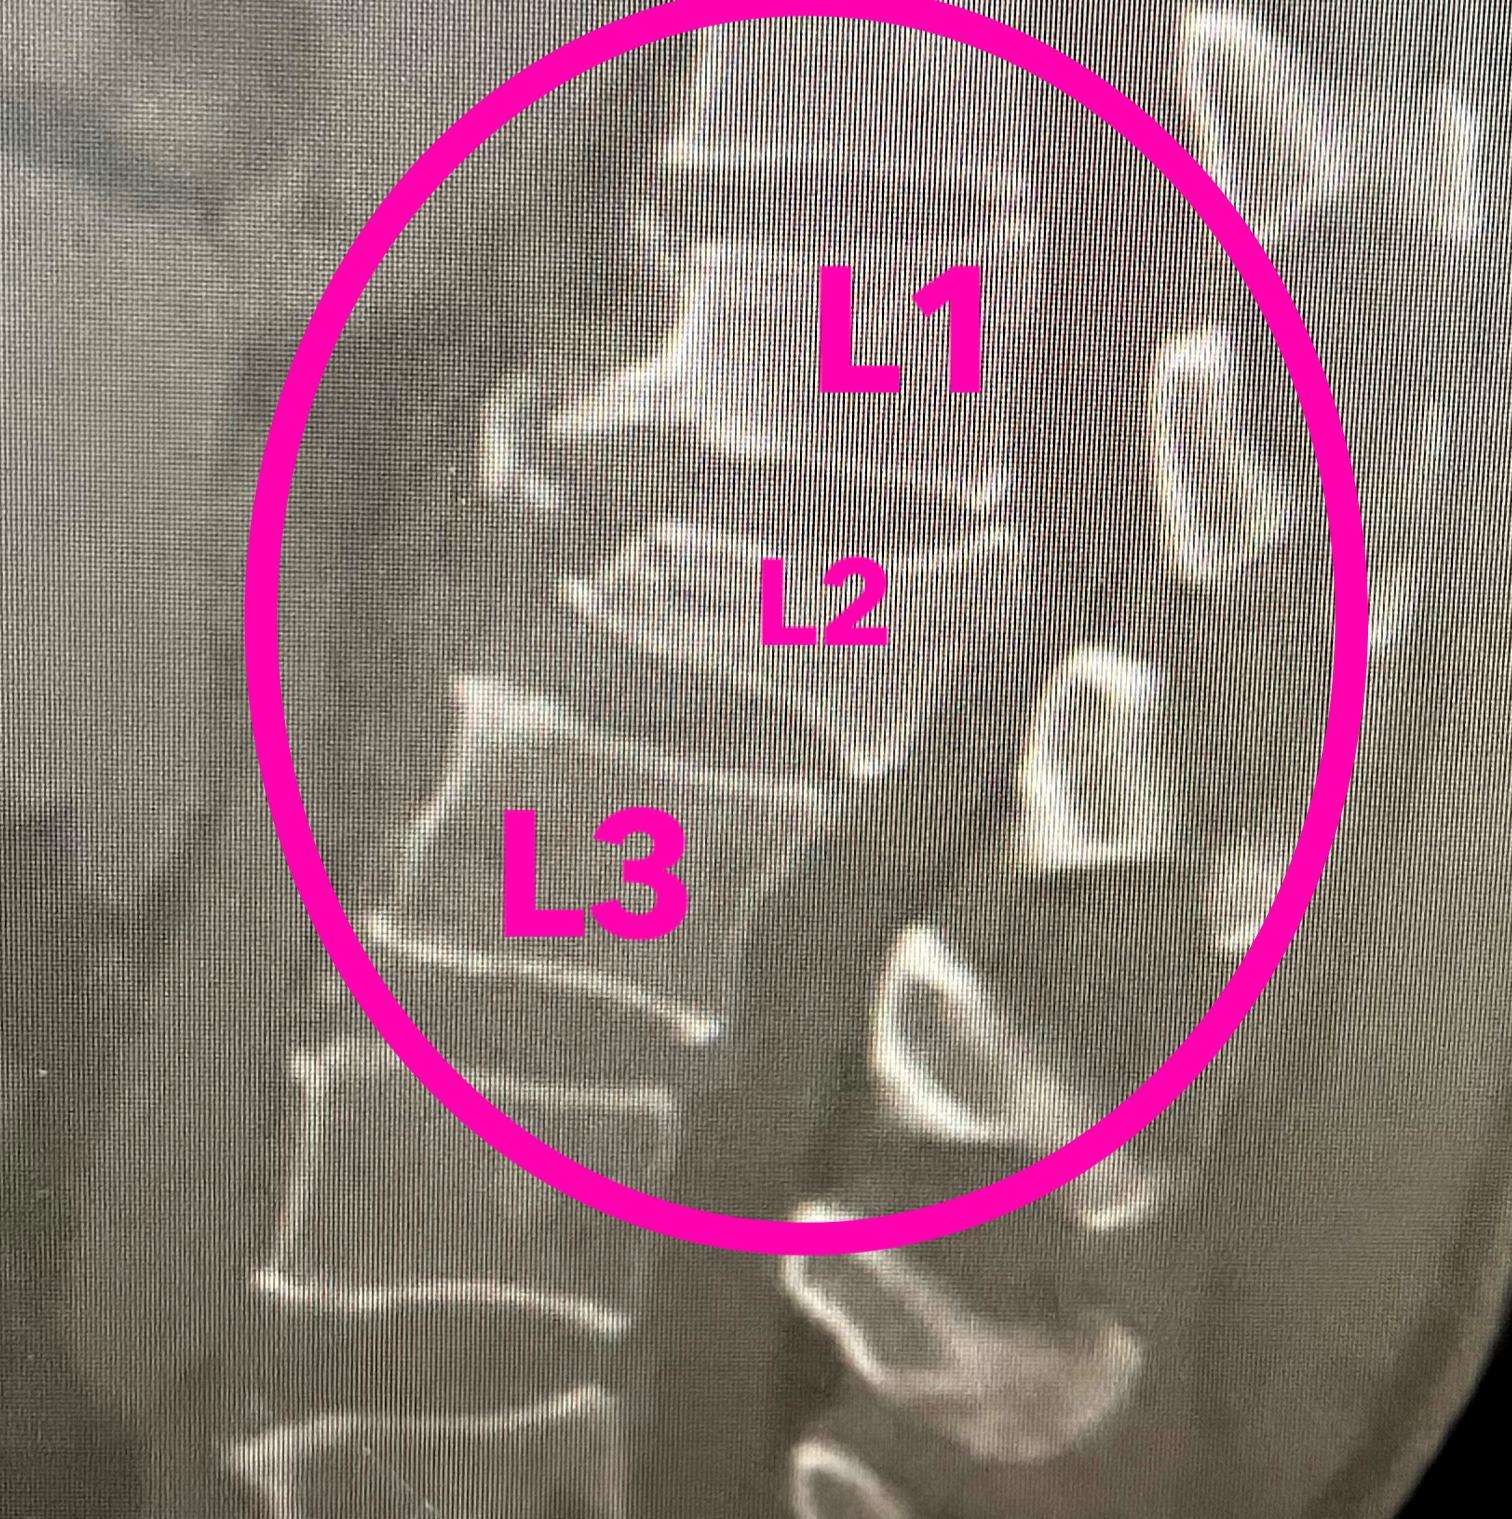

术前影像:腰椎爆裂性骨折(B2)、后凸畸形、脊髓损伤(ASIA B级)、马尾神经受压